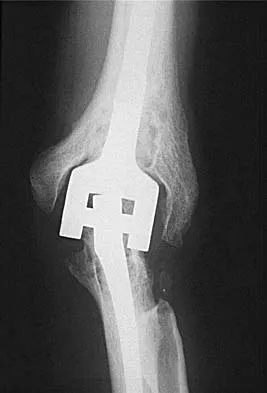

Figure 3 shows the AP radiograph of a patient with diabetes mellitus who has knee pain. A semiconstrained knee prosthesis was used in this patient to prevent which of the following complications?

Explanation

The radiographic appearance of the joint is highly suspicious for neuropathic joint (Charcot's joint). Evidence of bone loss on both the tibial and the femoral sides may necessitate the use of metal and/or bone augments. Patients with a neuropathic joint often have excellent range of motion, and postoperative stiffness is not a problem. The main problem with these patients is instability that occurs secondary to ligamentous laxity. Use of a semiconstrained prosthesis prevents the latter complication. Parvizi J, Marrs J, Morrey BF: Total knee arthroplasty for neuropathic (Charcot) joints. Clin Orthop 2003;416:145-150.